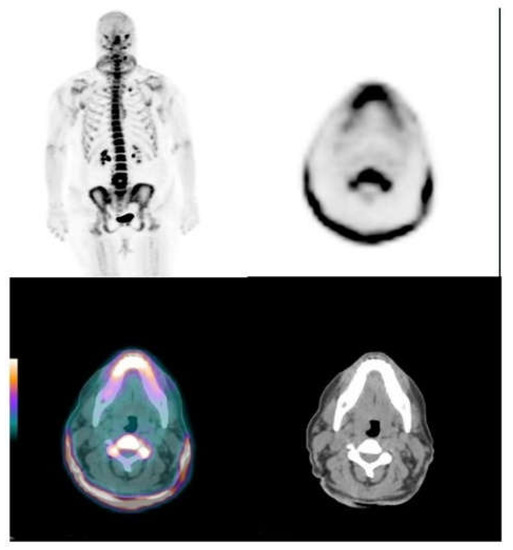

3.2. Skin and Vascular Uptake of 18F-NaF